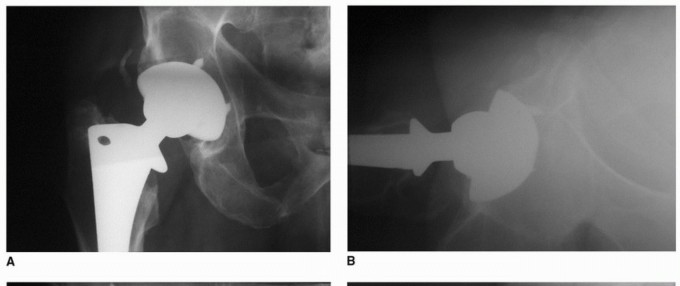

هشاشة العظام حول مفصل الورك الاصطناعي هي تآكل عظمي شائع بعد جراحة استبدال مفصل الورك الكلي، غالبًا بسبب جزيئات البولي إيثيلين. يبدأ العلاج بالتشخيص الدقيق عبر الأشعة المقطعية، ويُعد تبديل بطانة البولي إيثيلين حلاً فعالاً للمكونات الثابتة، مما يقلل الألم ويستعيد وظيفة المفصل بفضل خبرة الأستاذ الدكتور محمد هطيف.

الخلاصة الطبية السريعة: هشاشة العظام حول مفصل الورك الاصطناعي هي تآكل عظمي شائع بعد جراحة استبدال مفصل الورك الكلي، غالبًا بسبب جزيئات البولي إيثيلين. يبدأ العلاج بالتشخيص الدقيق عبر الأشعة المقطعية، ويُعد تبديل بطانة البولي إيثيلين حلاً فعالاً للمكونات الثابتة، مما يقلل الألم ويستعيد وظيفة المفصل بفضل خبرة الأستاذ الدكتور محمد هطيف.

يتناول هذا المقال الأسباب والتشخيص وخيارات العلاج لهشاشة العظام التي تحدث حول مكونات الحُق الثابتة ![توضيح طبي: هشاشة العظام حول مفصل الورك الاصطناعي تبديل بطانة البولي إيثيلين الحل الأمثل](/media/upload/ad023e43-fc70-4c74-a667-a1eb6d8e107d.jpg) ![توضيح طبي: هشاشة العظام حول مفصل الورك الاصطناعي تبديل بطانة البولي إيثيلين الحل الأمثل](/media/upload/e718bae5-3e04-4049-b408-451d4ebed9ed.jpg) ![توضيح طبي: هشاشة العظام حول مفصل الورك الاصطناعي تبديل بطانة البولي إيثيلين الحل الأمثل](/media/upload/436dcac0-c732-444a-8403-539f5c46ae88.jpg) ![توضيح طبي: هشاشة العظام حول مفصل الورك الاصطناعي تبديل بطانة البولي إيثيلين الحل الأمثل](/media/upload/5295a9df-4504-4c8c-89b3-71233cb41476.jpg) ![توضيح طبي: هشاشة العظام حول مفصل الورك الاصطناعي تبديل بطانة البولي إيثيلين الحل الأمثل](/media/upload/c2411af8-be23-4562-90d6-94b6e9d0c0d9.jpg) ![توضيح طبي: هشاشة العظام حول مفصل الورك الاصطناعي تبديل بطانة البولي إيثيلين الحل الأمثل](/media/upload/eda756a8-6677-4b09-b6f5-3619857552e2.jpg) ![توضيح طبي: هشاشة العظام حول مفصل الورك الاصطناعي تبديل بطانة البولي إيثيلين الحل الأمثل](/media/upload/d199b219-f355-4caf-85c3-a764f4913cb3.jpg) ![توضيح طبي: هشاشة العظام حول مفصل الورك الاصطناعي تبديل بطانة البولي إيثيلين الحل الأمثل](/media/upload/ddd6b344-5b51-450e-8239-8e832b923988.jpg) ![توضيح طبي: هشاشة العظام حول مفصل الورك الاصطناعي تبديل بطانة البولي إيثيلين الحل الأمثل](/media/upload/86786efa-0a81-438c-984d-749c462862d5.jpg) ---